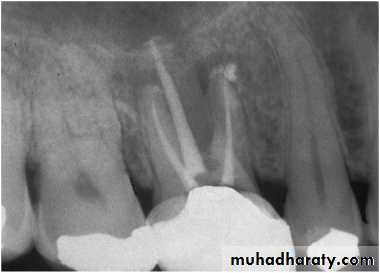

Gutta Percha POINT TRACING

Can localize the endodontic lesion to the specific tooth.Aids in the differential diagnosis between a periodontal and an endodontic lesion.

Placing a gutta percha point through the sinus/fistula tract and take a radiograph.

Radiographs IMPORTANCE

Provides information on the extent of caries in to the pulpNo. of root canals and accessories

The course & shape of the canals

Length of the root

CalcificationsResorptions

PDL status8. Nature of periapical area & alveolar bone

9. Root fractures10. Differentiation of pathosis